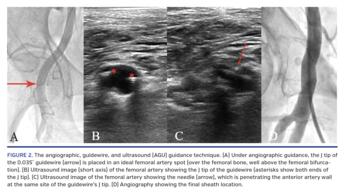

Angiographic, guidewire, and ultrasound (AGU) guidance. We integrated several different techniques to create the AGU guidance technique (see Figure 1 for schematic representation), which is specifically designed with the aim of facilitating the achievement of a precise femoral entry in patients with complex anatomy undergoing procedures requiring large femoral sheaths with simultaneous use of other arterial accesses. The AGU guidance technique consists of the following steps (Figure 2):

- Under angiographic guidance, a .035˝ J-tip guidewire is placed in the “angiographically ideal” site (wider femoral artery diameter, no calcium, etc) for femoral artery access (Figure 2A).

- The J-tip of the guidewire is identified inside the femoral artery (Figure 2B) by ultrasound (confirming the vessel quality at the spot identified on angiography), which is also used to guide the advancement of the needle toward the anterior wall (Figure 2C).